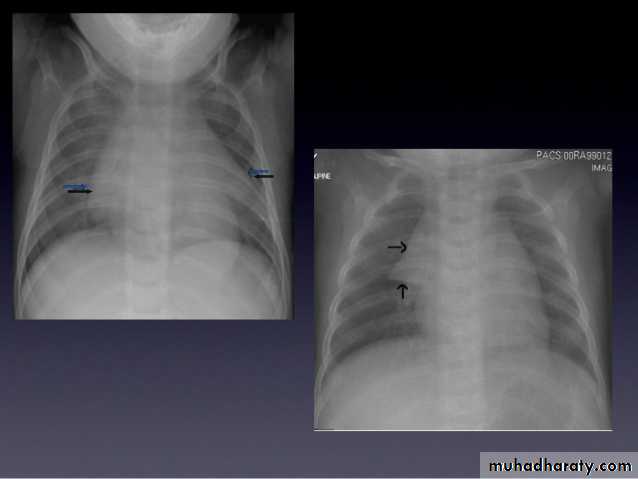

What is the main difference between 2 films ??? What is the shape of each one ??? A. B.

44.A.RT middle lobe consolidation

Homogenus opacity of right middle lobe triangular in shape, the fissures are normal

B.RT middle lobe collapse

Homogenus opacity of right middle lobe tongue like with elevation of the fissure